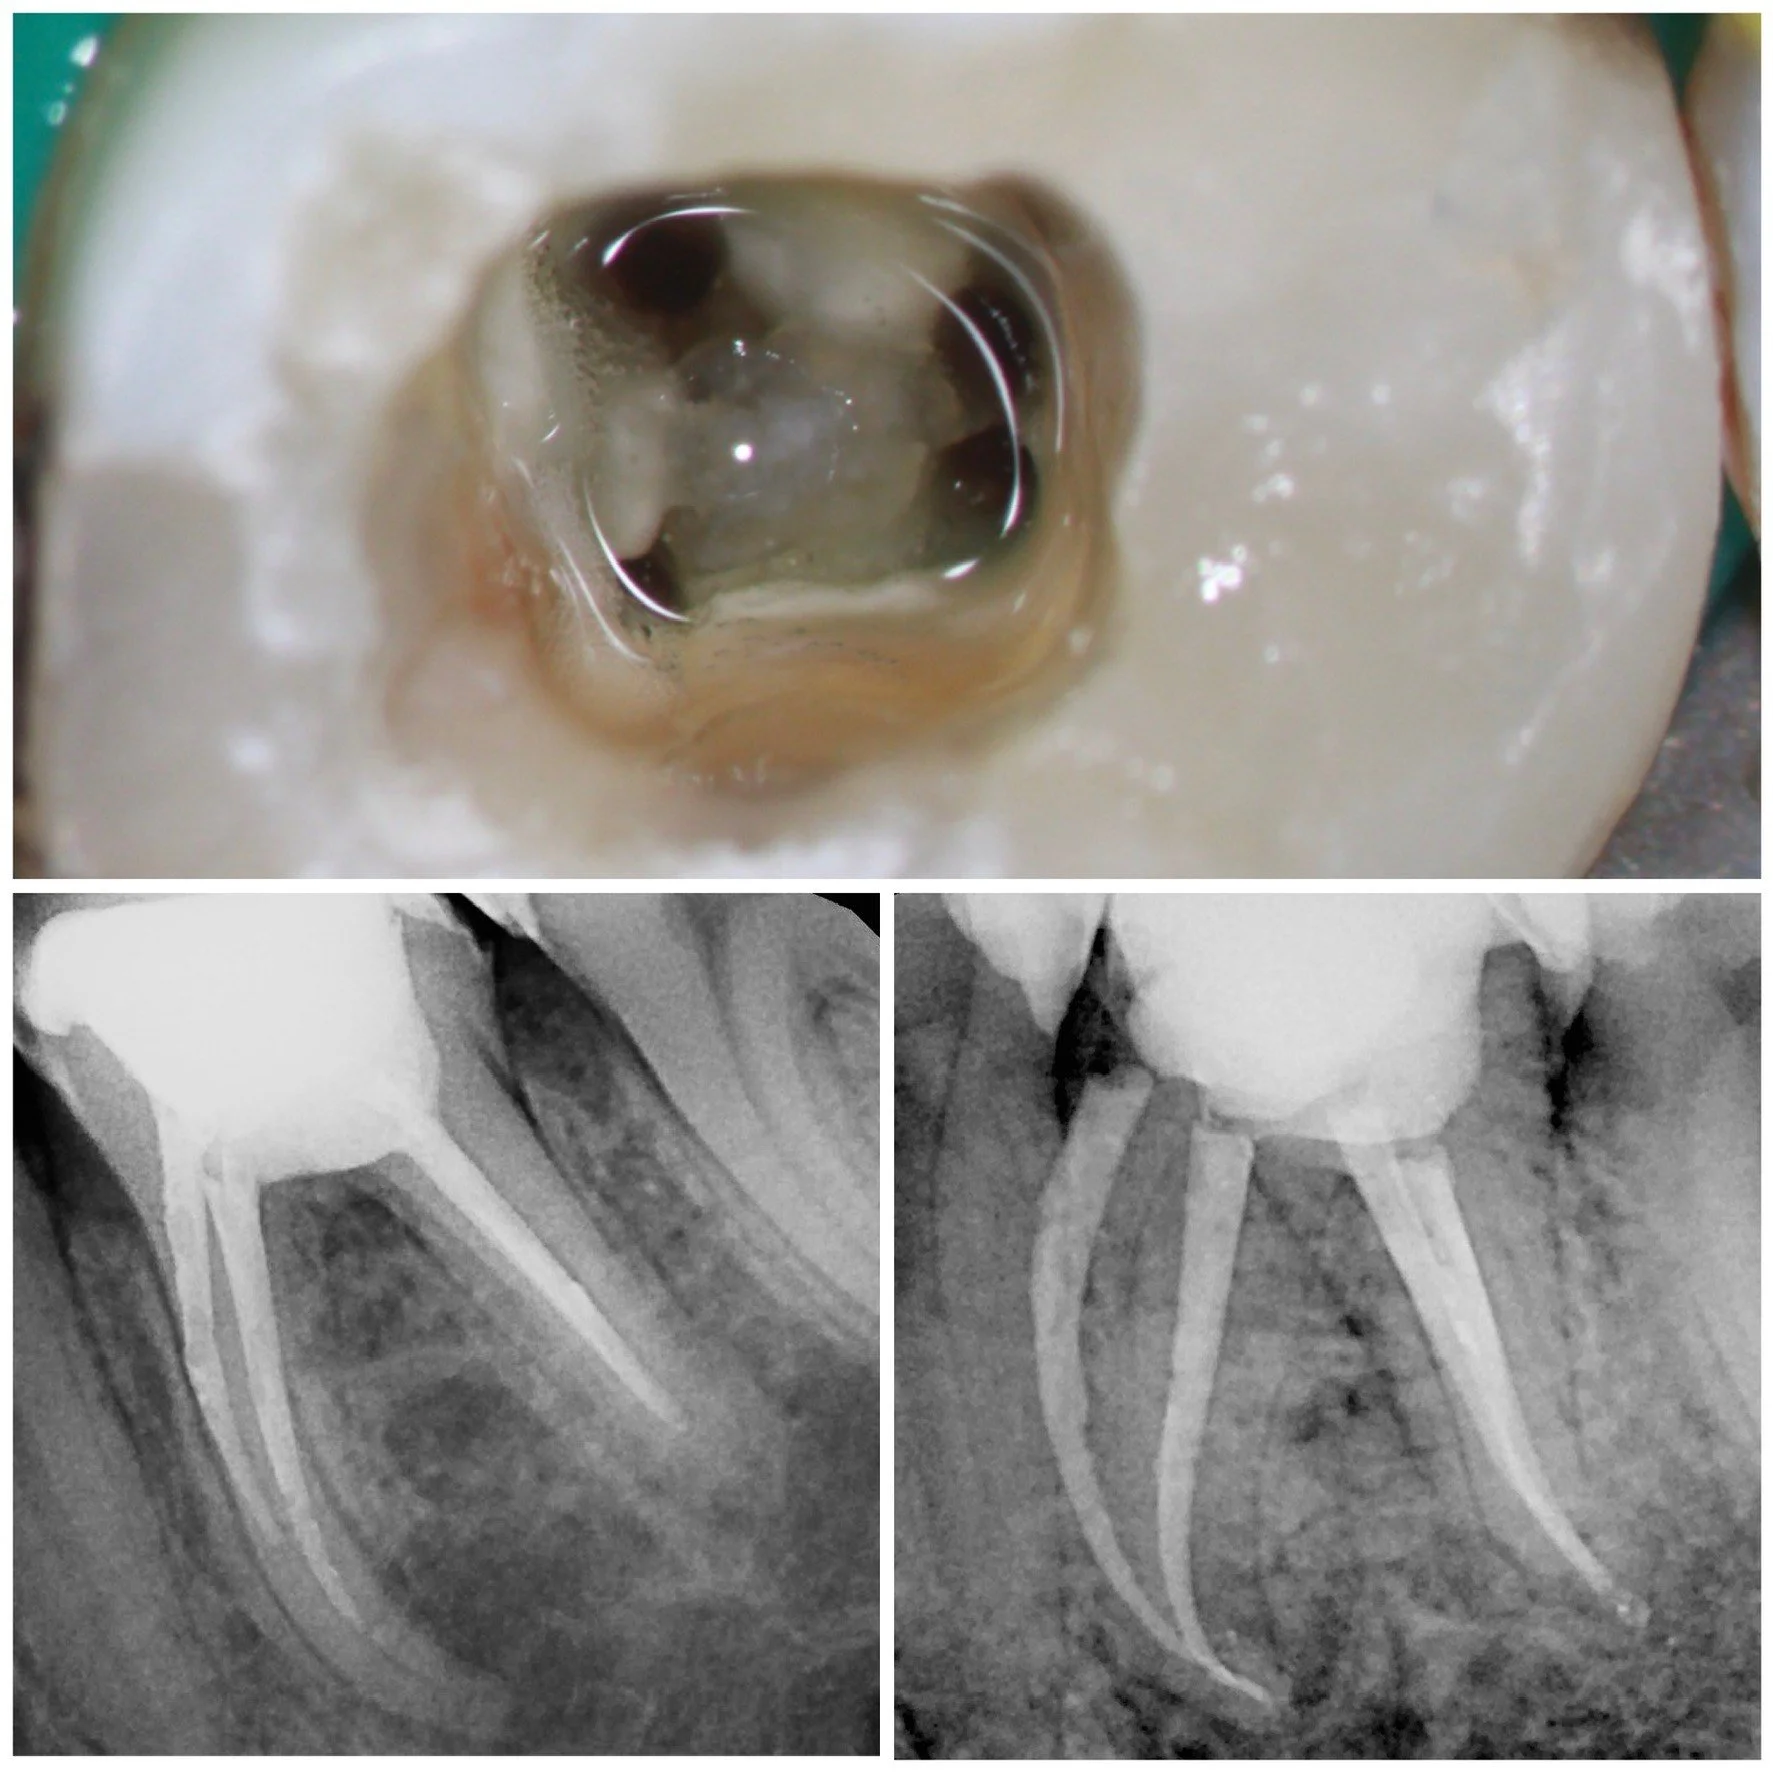

Me considero una privilegiada en poder conservar las piezas dentales, conociendo la variabilidad anatómica del sistema de conductos, y lo complicado que resulta en ocasiones poder manejarlos

En una estancia clínica conmigo es habitual ver casos de endodoncia, retratamientos, traumatismos, cirugía apical, terapia pulpar vital, perforaciones, ápices inmaduros, grandes complejidades anatómicas

¿Qué tratamientos podrás presenciar? Casos de endodoncia, retratamientos, traumatismos, cirugía apical, terapia pulpar vital, perforaciones, ápices inmaduros, grandes complejidades anatómicas